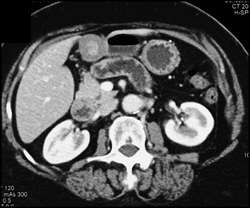

Vascular Polyp in Antrum C/w Cancer Bx Was Inflammatory